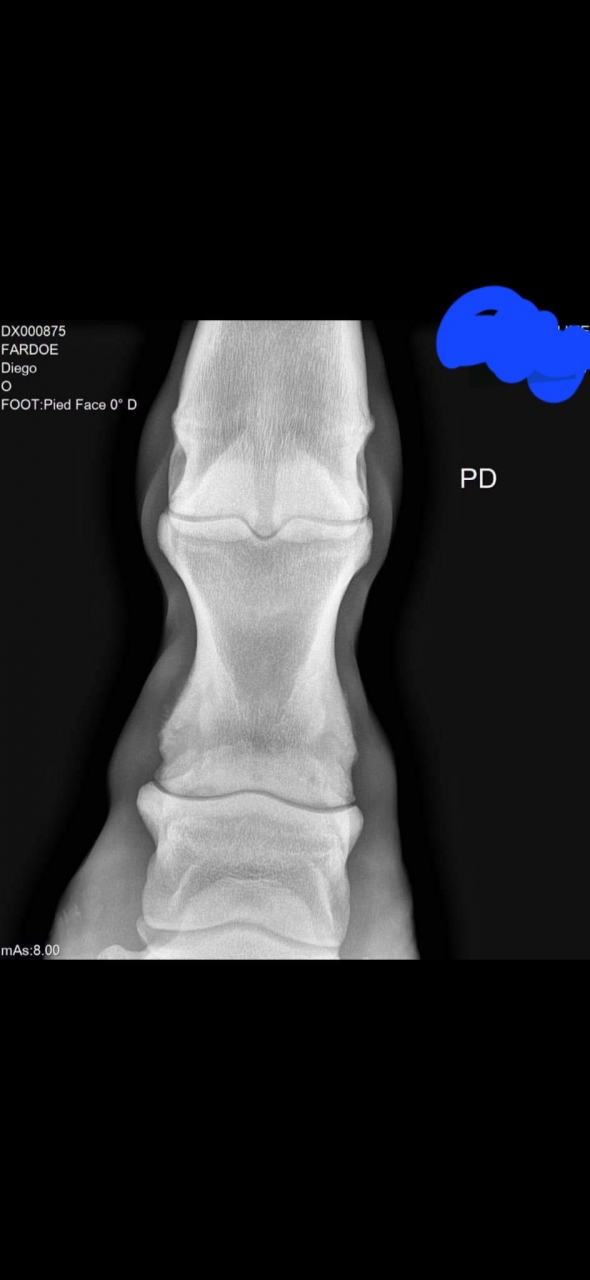

| Dire merci | ![]() Avec ce genre de radio, et légère déformation du paturon est ce que quelqu'un aurait une une idée des risques? Le cheval ne boite pas. C'est pour ma culture personnelle |

| Dire merci | L’extrémité distale de P1 me semble quand même très remaniée ? ![]() Enfin je ne suis pas experte en lecture de radio, mais le bord latéral est pas bien joli je trouve. Bon clairement, vu le cheval, les clichés, le contexte… c’est peut être pas l’idée du siècle Ça serait intéressant de faire un post de lecture de radios, avec le CR ensuite. Ça peut être instructif ![]() |

| Dire merci | Moi je dis qu'une radio juste de face bonjour bonsoir pour interpréter quelque chose a fortiori si on a pas l'autre membre. |

| Dire merci | Sur cette radio, perso je vois un affaissement de p3 et p2 par rapport a p1. Car p1 est bien parallèle au sol, alors que p2 et p3 sont inclinés :![]() J'imagine que le cheval compense la mauvaise repartition des charges dans le pied pendant un temps sans qu'il n'y ai de conséquence visible, mais est-il possible de corriger le tir avec un bon pareur ou maréchal avant que ça ne s'aggrave et que le cheval ne boîte? Aucune idée. Avis aux spécialistes? |

| Dire merci | J'ai des radios des boulets de Grimm que je suis retourné voir pour comparer. Je trouve les radios de mon poney plus jolies, avec mon oeil de béotien, et il a, je cite le rapport : Remodelage péri articulaire des boulets, épaisseur des cartilages faible, sclérose de l'os sous chondral. Ici, le souci je le vois sur P2, sur le bas, avec un remodelage non ? Sans doute consécutif à ce que souligne très justement pam Mais aussi en haut de P2. Mon poney a peu de cartilage selon le rapport, mais il y a plus "d'espacement" entre les os comparé au cheval noir. Je vais essayer de mettre des photos du mien, sachant que j'ai tout sur un PDF, donc ce n'est pas commode à extraire. Je précise bien que la radio portait sous les boulets, je n'ai pas plus bas sur ce type de vue arrière pour vraiment comparer. Et oui, ce sont de petites baguettes de Welsh B, pas la même épaisseur d'os J'avais fait des radios car je trouvais que ses boulets postérieurs avaient tendance à craquer, et il y a une gêne effective. La véto, au test locomoteur, m'a dit qu'elle aurait émis un avis positif sur une visite d'achat. Après radios, elle était plus réservée sans que ce soit une cata non plus. ![]() ![]() |